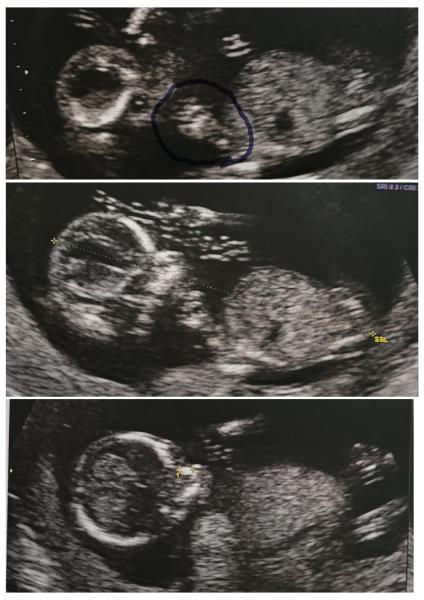

Hallo ihr Lieben 😊   Wir hatten heute auch endlich wieder einen US Termin.    Nackenfalte und Nasenbein sind unauffĂ€llig. Das beruhigt uns sehr. Auch alles weitere sah top aus 😊 Man konnte sogar schon die 4 Kammern im Herz sehen (meine Fa war davon selbst begeistert 😄).    Leider wollte das Kleine bei den Bildern nicht ganz so mitmachen. Es hatte sich viel bewegt und die Arme oft oben am Kopf... Auch mal uns kurz seinen RĂŒcken und Fuß gezeigt 😊 (ist in dem einem Bild eingekreist).. aber trotzdem hat meine Fa nochmal schöne Bildchen eingefangen đŸ„°Â    Auch haben wir heute das Blut fĂŒr den NIPT abgenommen plus der Geschlechtsbestimmung. Mit GlĂŒck kommt das Ergebnis noch innerhalb der nĂ€chsten Woche đŸ€©đŸ€ jetzt sind wir wirklich wahnsinnig aufgeregt was es wohl nach unseren zwei wundervollen MĂ€dels diesmal wird đŸ€­Â    Der nĂ€chste Termin ist dann erst wieder in 4 Wochen. Da haben wir ja fast schon Weihnachten. Wahnsinn wie die Zeit rennt oder? 🙈 Obwohl sich das Warten immer so ziecht bis zum nĂ€chsten Termin..    Wie geht es euch?    Lg und alles Gute weiterhin 🍀

Bild zu Update Screening 😊 - Forum fĂŒr Mai - Mamis